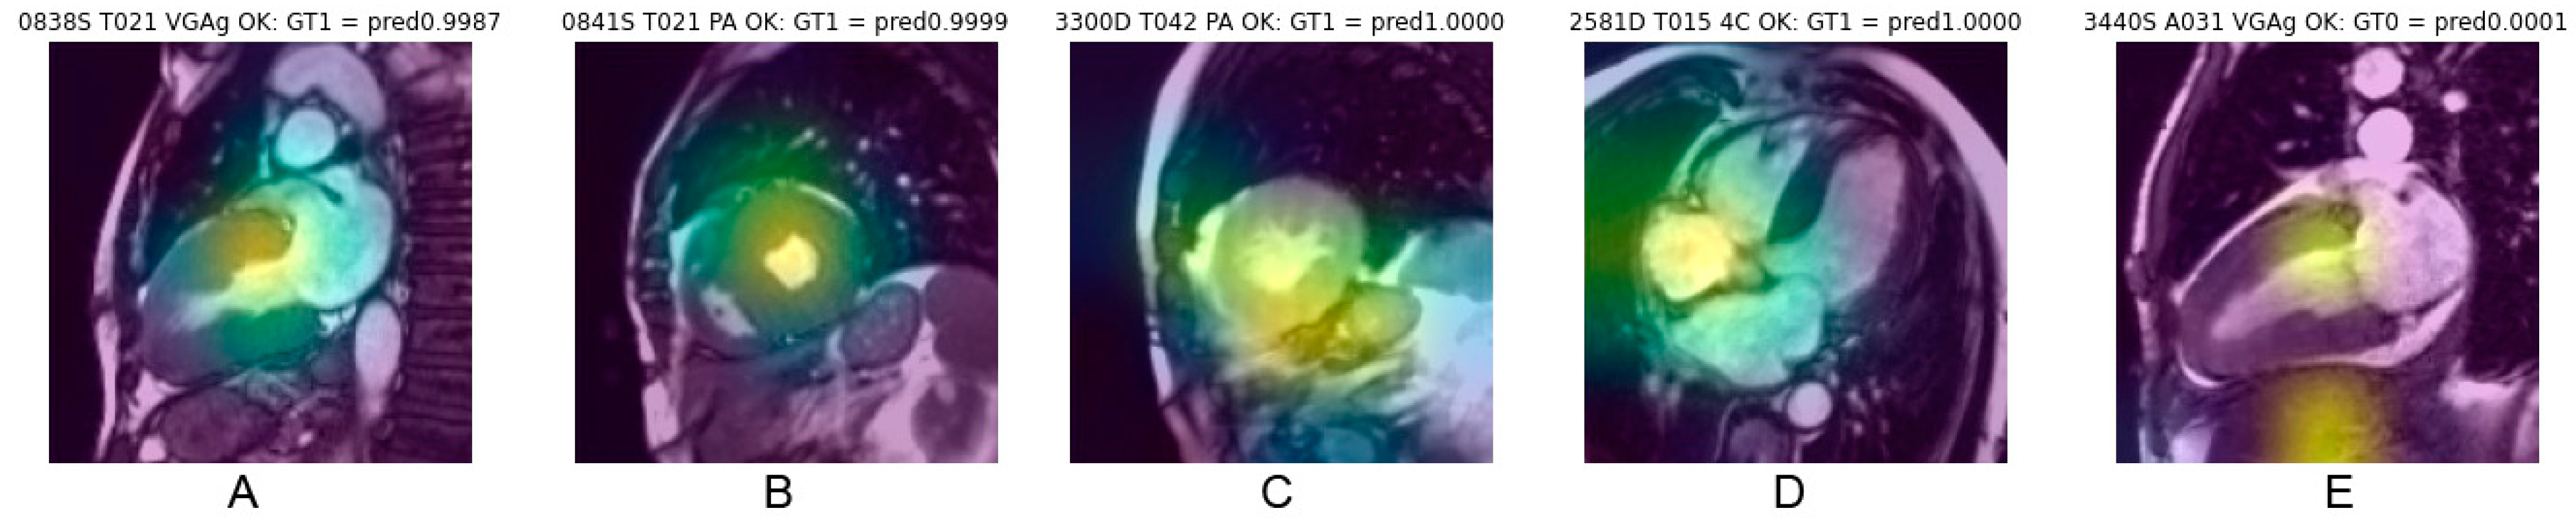

3.5. Analysis of Saliency Maps for cineMR Images